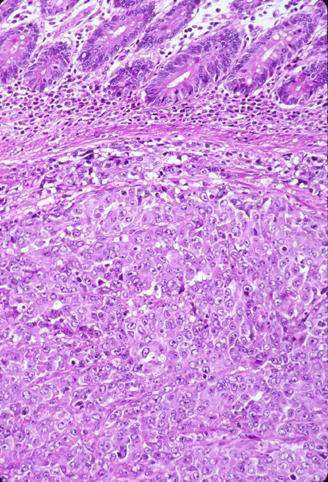

背景色の変更[ 画像ID:2354 ] 肺癌から多発性に小腸に転移した切除例(56才,女性)の病理組織像(ミクロ) 強拡大像です。腫瘍細胞は大きく、大型で卵円形から多形成の核を持ち、核小体も目立ちます。また、腺管形成を伴わず増殖形式はsolidです。特異な配列は認められず、大細胞癌または未分化癌の所見です。 ■詳細データ